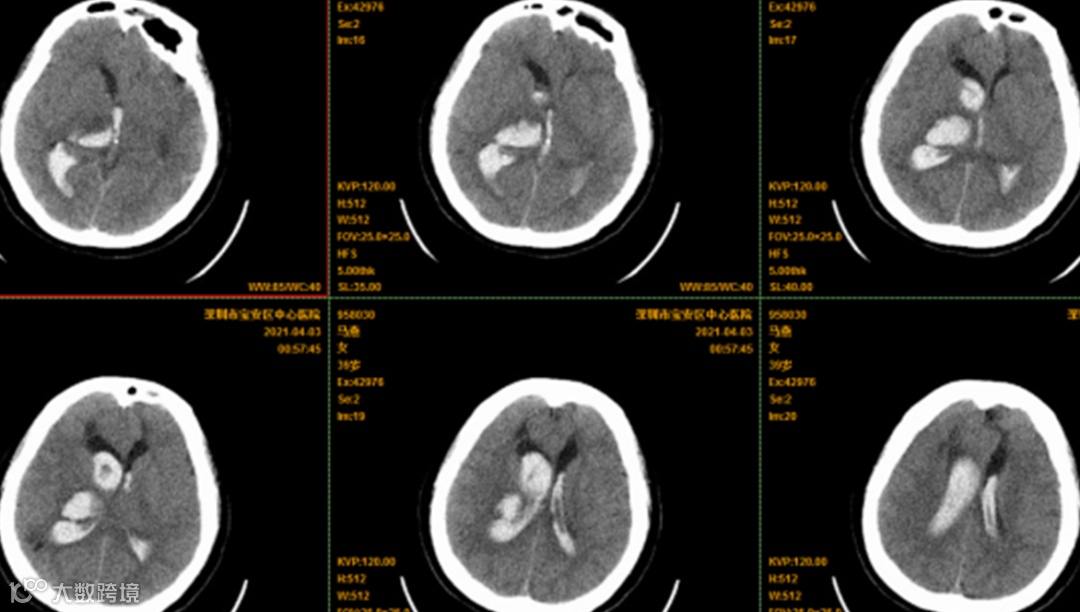

凌晨01:00,宝安区中心医院120急救车送来一名39岁在家突然昏迷的烟雾病患者。急查其颅脑CT:右侧丘脑出血破入脑室、急性梗阻性脑积水。患者病情危重,等手术抢救工作全部顺利完成,已凌晨4点多。

术前颅脑CT: